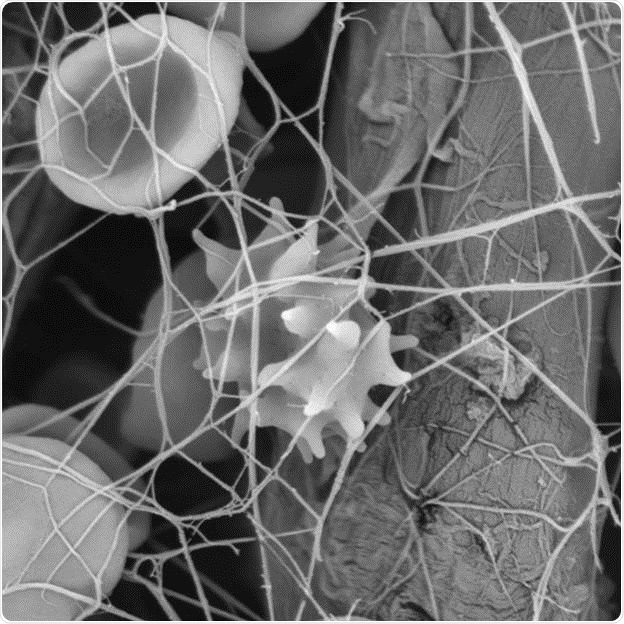

Figure 1: Each wounding causes a reaction by the body-  This is the example of a fibrin network with blood cells images with scanning electron microscopy.

Blood disorders are a different class of blood diseases that occur due to insufficient blood clotting caused by lack of thrombocytes or other components involved in the blood clotting process. In case of an injury, in normal conditions, clotting factors and fibrin present in the blood allow binding of thrombocytes with each other to form a plug at the affected site to avoid further hemorrhage and facilitate healing of the injured tissue.

Blood research has turned out to be an increasingly popular research field to gain insights into the interactions taking place during clot formation. For this purpose, the SEM has been shown to be very useful, enabling scientists to easily observe the 3D structures of blood clots and the interactions taking place between the blood cells and different fibers.